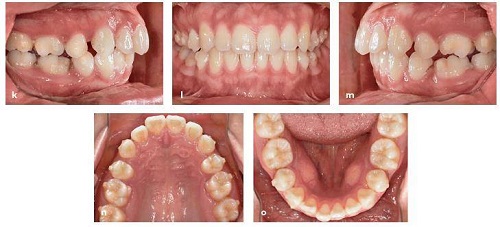

Tại tháng 14 trên giao thức thay đổi khay 2 tuần một lần, khoảng nhổ răng đã được đóng (Hình 13-16k đến 13-16o).

Hồ sơ tiến độ tại tháng 14 với khoảng nhổ răng được đóng lại. Một số tipping phía gần của răng hàm lớn thứ nhất được thấy. (p) Tiến hành chụp phim toàn cảnh panorama cho thấy các răng hàm lớn thứ nhất đã tipping về phía gần vào vị trí nhổ răng.

Tuy nhiên, chụp ảnh toàn cảnh panorama tại thời điểm đó cho thấy tất cả các răng hàm lớn thứ nhất đã tipping về phía gần vào khoảng nhổ răng .